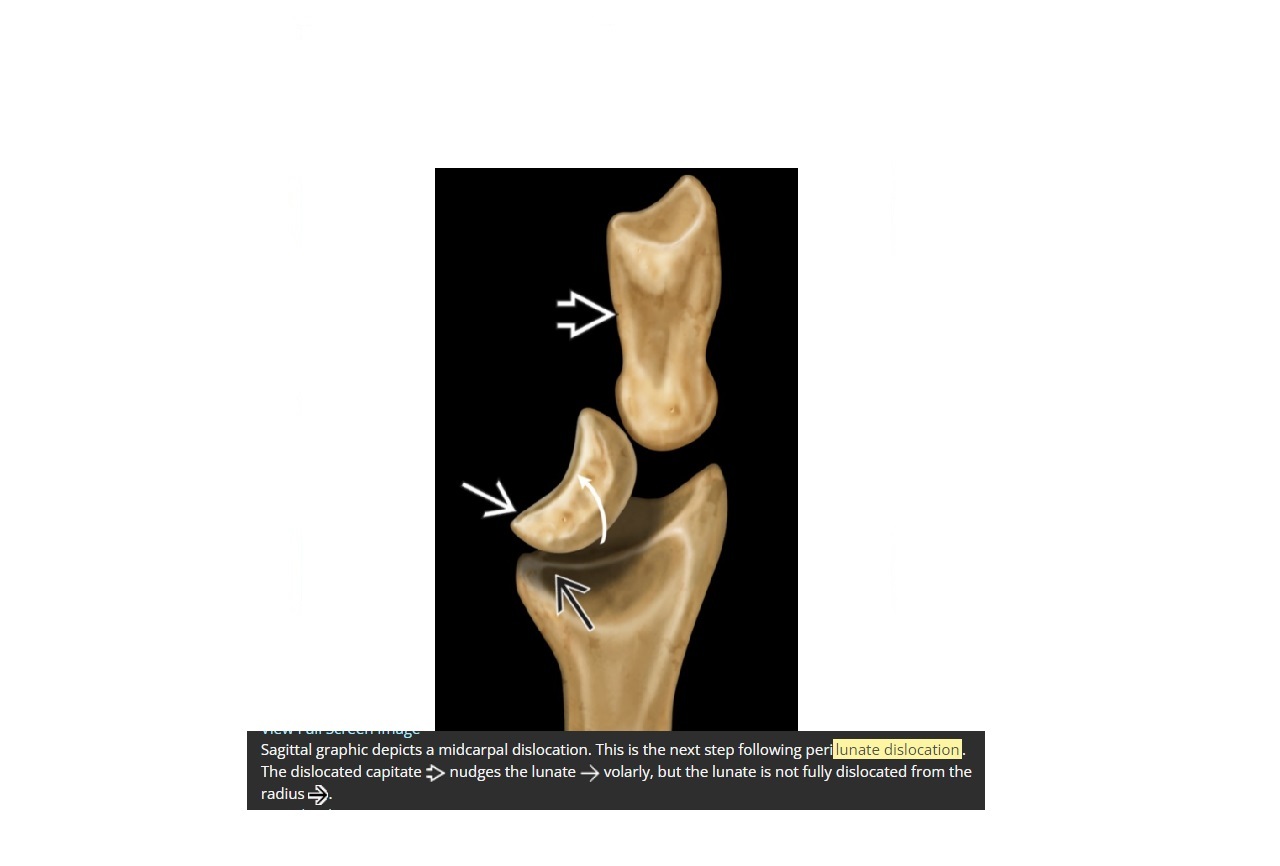

What is midcarpal dislocation. what ligament is damaged? What associated fracture ?

capitate is dislocated dorsal and nudges the lunate volarly but it is not fully dislocated

Ligament = Triquetrolunate interosseous ligament

Associated with Triquetral fracture